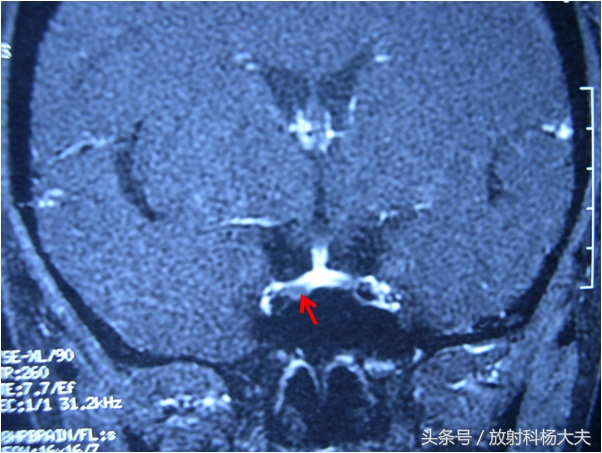

下图红箭所示的小黑点就是那个小瘤子,原来那个医院做的垂体MRI非常棒,做这种检查一定要做动态增强扫描,也就是打了药后不停地进行扫描,垂体瘤会在某一期,表现为低信号。这个扫描虽然不是什么高精尖的扫描技术,但也挺考验医院水平的,假如按照常规的扫描方法,很可能竹篮子打水一场空,瘤子明明就在那里,你却看不到。